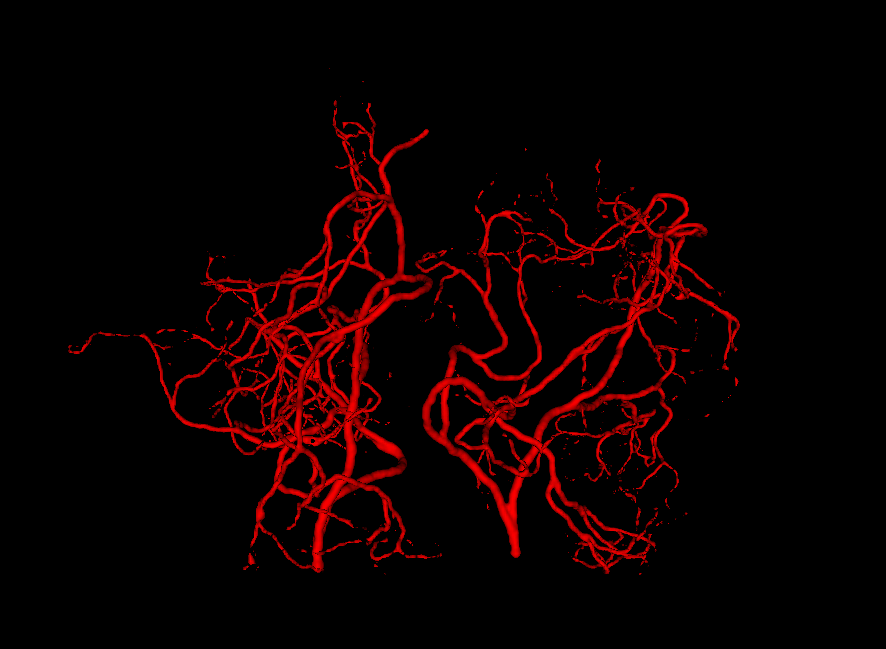

The radius of the vessel is tied to the direction vector of it’s nodes. Each node is represented as a sphere with center at a given node’s position vector p𝑝\vec{p} and with radius proportional to the direction vector magnitude r=βd𝑟𝛽norm𝑑r=\beta\|\vec{d}\|. With enough overlap between spheres (β>1.0𝛽1.0\beta>1.0), a tube-like structure is approximated. The binary vessel structure can be obtained in 3-dimensional pixel space through rasterization of the tree nodes into voxel space. The value of β𝛽\beta not need be much larger than 1.01.01.0 for the rendered vessels to appear realistic, as the resolution of a CTA scan is always too low compared to the size scale of the imperfections arising from this approximation. We empirically set a node’s starting β𝛽\beta value to 3.0, as even in branches that had their radii reduced due to bifurcations taking place in earlier nodes (while having parent-child distances preserved), no visible width disturbances could be observed (see Figure 3.2).

Refer to caption

Figure 3.2: Generated vessel structures with no spatial target growth incentive. The right figure was grown in a small spatial volume relative to the root width, while the left was grown unconstrained by volume.

Figure 3.3: Generated vessel structures with spatial target growth incentive. The target volume was a vessel density atlas created by averaging the ground truth of patients in our data set.

An approach was also introduced to make the global vessel distribution mimic the one found in the brain. The brain arterial system is designed to supply the entire brain, yet the current structure described so far grows away from the root node and is unlikely to meaningfully fill the volume of the brain once rendered. To solve this issue, a density atlas was created out of the patients scans in our data set to assign a volume with probabilities of an artery being present.

Another use of the vessel atlas is to determine if a node is out of bounds. This is done by checking if the atlas has a value of 0 at the node’s position. If a leaf node is too far out of the brain, the branch is discontinued (the leaf will never be selected to spawn a child). On top of this, in order to make the overall structure more realistic, a different atlas was used for each of the two hemisphere root nodes. Such atlas would only have non-zero values for one brain hemisphere. This causes the resulting vessel structures to no longer cross over between hemispheres. A resulting example structure can be seen in Figure 3.3.